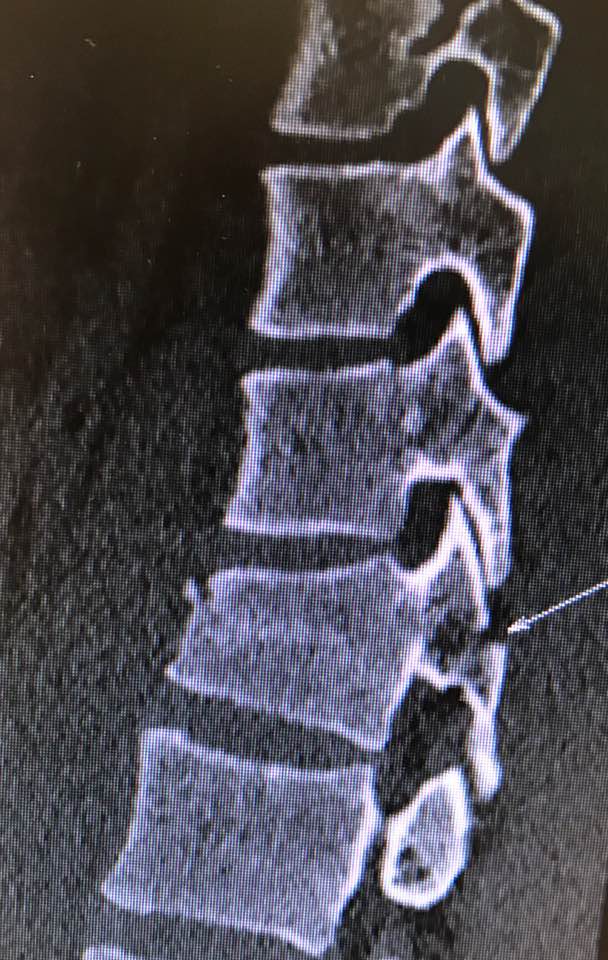

嚴重的工業意外受傷,T12胸脊椎不穩定的3段(前、中、後柱列)壓迫性脊柱椎體骨折

1. 即使您的胸部及胸脊椎柱被8英尺高和200磅重的巨大雪櫃嚴重壓碎, 您仍然生存, 您的中樞脊髓神經但沒有受到傷害.

2. 即使公立醫院忽畧了你不穩定的前、中、後3柱列的T12胸脊椎骨折,並在3天後容許你出院送回家, 你到私家醫院再進行第二次詳細檢查!

3. 幸運的是,入院前及兩天來你未有因為不穩定的脊柱椎體骨折碎片的移位而導致你脊髓中樞神經到不可逆轉和永久性的損傷致雙腿癱瘓及大小便失禁. 今天所有穩定你碎裂脊椎的手術都做完了.